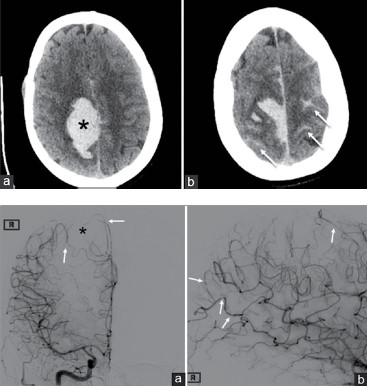

Paciente do gênero feminino, de 35 anos de idade, 10 dias após o parto, procura o serviço de neurologia com quadro de cefaleia occipital, de forte intensidade, que se iniciou 2 dias antes da consulta; apresenta também moderada confusão mental, náuseas, vômitos e dificuldade de deambulação. Ao exame neurológico, paciente normotensa, ritmo cardíaco normal e se constata hemiparesia e hemihipoestesia esquerda. Exames de neuroimagem são apresentados a seguir.

Considerando esses elementos, qual seria a sua primeira hipótese diagnóstica?